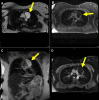

Case summary: We present the atypical presentation of a progressive, left-sided pericardial cyst. The patient underwent surgical resection with recurrence within 5 months.